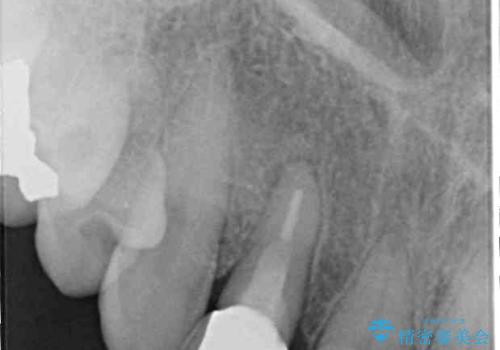

- 前歯のクラウン周りに歯肉が腫れていることを気にして来院された患者様です。

元々磨き残しによる歯肉の腫脹がありましたが、クラウンが歯肉深くに装着されていたため、特に腫脹が目立っていました。

仮歯に置き換えた際に歯周外科処置を行い、歯肉の腫脹が落ち着いたことを確認してオールセラミッククラウンにて補綴することとしました。